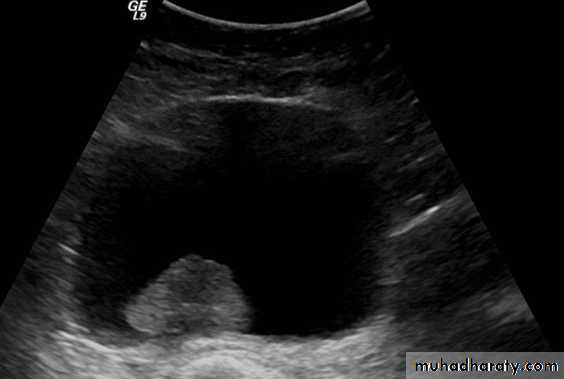

Also to prevent retention of urineWhat's this imaging study?What the abnormal finding?

Wilms tumor deviating the kidney ant. Upward

Big should be reduced by chemo then surgeryWhat's this test?

• UPJ obst. Ureteric stricture and dilation of renal pelivsCan you grade this Reflux?